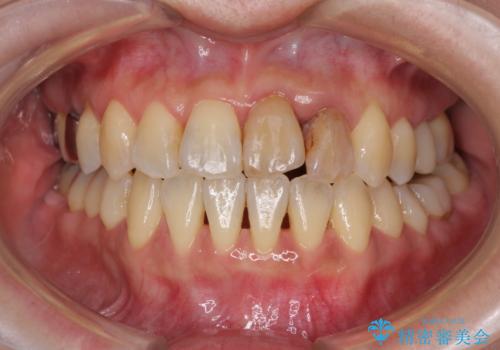

- 前歯の反対咬合により、日々強い痛みを感じているとのことで来院された患者様です。

骨格的に下顎が前方位にありますが、歯列矯正で前歯の被蓋関係を改善することができると判断されたため、インビザラインにより矯正治療を行うこととしました。

また、上顎前歯と下顎大臼歯に神経を取り除いた歯があったため、矯正治療後に、セラミッククラウンにて補綴することとしました。

前歯が内側に倒れ込む力がかかり、正常な歯ぎしりもできないため、非常に負担のかかりやすい咬み合わせでした。

矯正治療中に上顎前歯が下顎前歯を乗り越える際は、前歯でしか咬めない状況が続くため、食事など不便を感じましたが、治療後には前歯の痛みもなくなり、安定した咬み合わせとなりました。